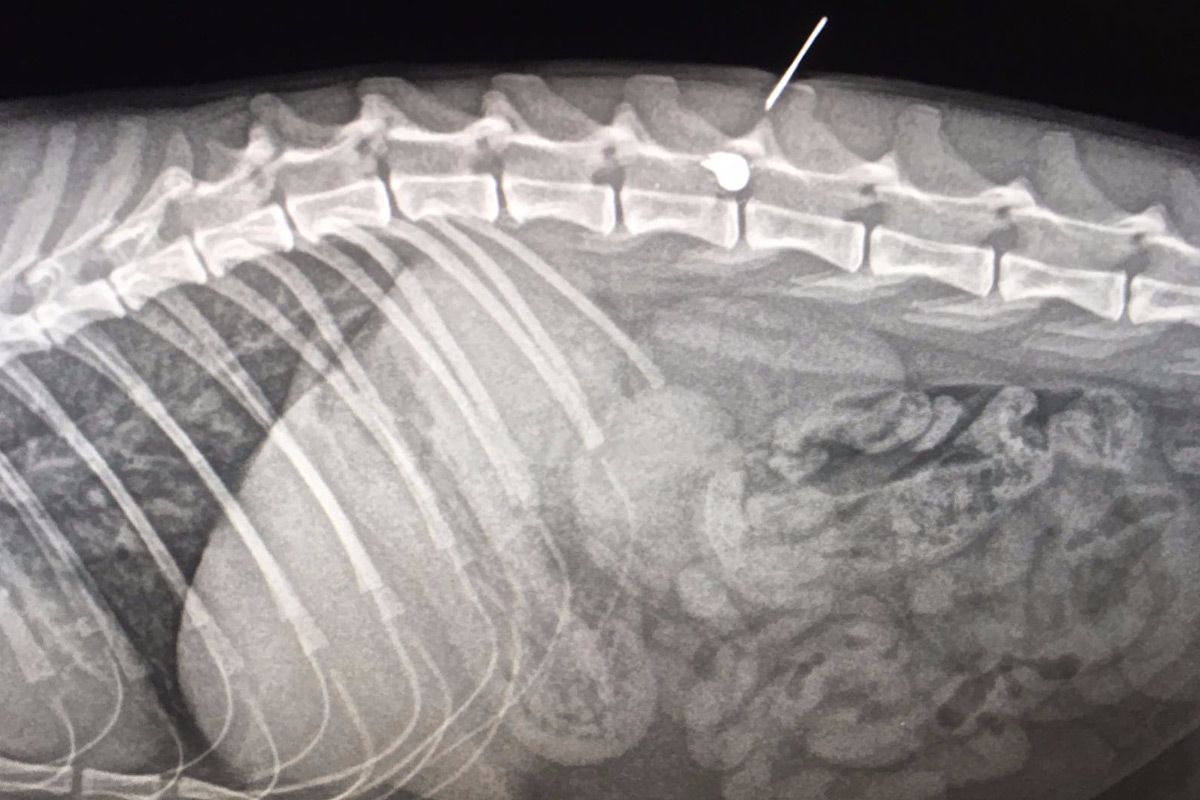

L’animal va ser traslladat a la clínica veterinària Triavet, col·laboradora de la Plataforma, on va ser atès d’urgència. L’informe veterinari va concloure que el gat, que ha estat batejat amb el nom de Live, havia patit un tret i tenia un perdigó allotjat a prop de la columna vertebral. Després, el Live ha estat intervingut al Centre Veterinària Girona pel Dr. santcugatenc Xavier Barnils, especialista en traumatologia.

En el millor dels casos no perdrà la mobilitat de les potes del darrera però necessitarà una llarga recuperació i mai tornarà a caminar correctament. De fet, el veterinari preveu que el gat s'hagi d'estar dues setmanes més ingressant.